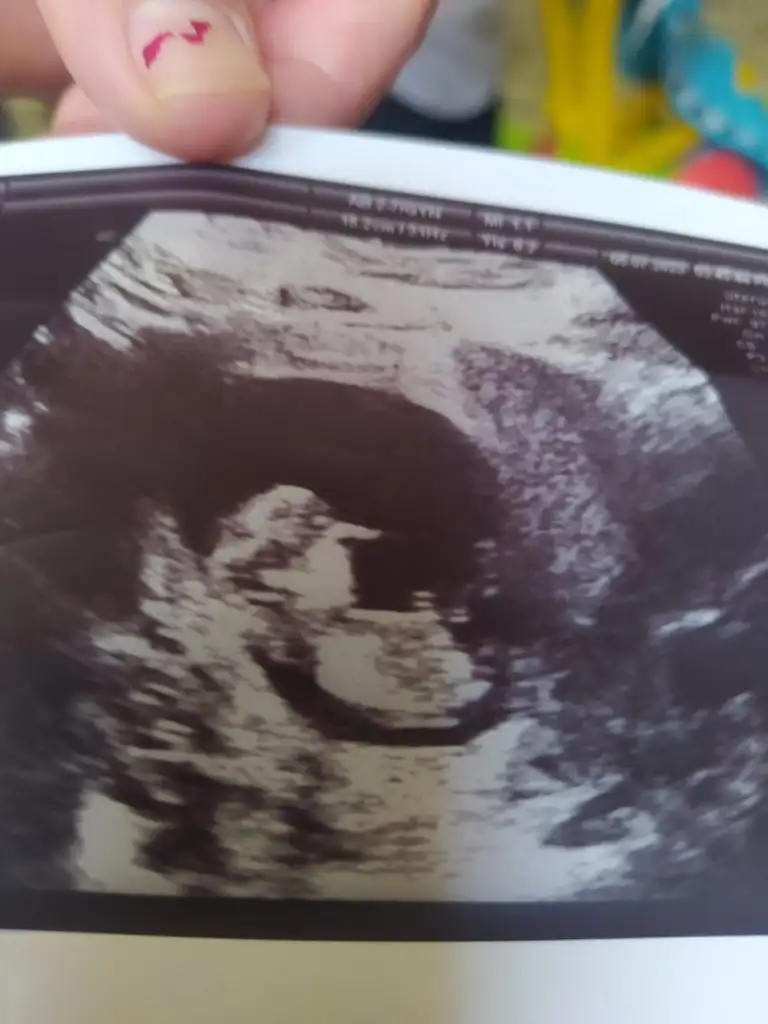

Selam arkadaşlar buraya bir arkadaşmn ultrason fotoğrafları atıyorum bir türlü cinsiyet oğrenemedi çok merak ediyor sizden ricam bir tahminde bulunabilirmsnz soyasosu canm sen anlıyordun dmi

• IMG-20230717-WA0006.webp

IMG-20230717-WA0006.webp

20,9 KB · Görüntüleme: 75

• IMG-20230717-WA0005.webp

IMG-20230717-WA0005.webp

19,6 KB · Görüntüleme: 77

• IMG-20230717-WA0004.webp

IMG-20230717-WA0004.webp

21,7 KB · Görüntüleme: 70